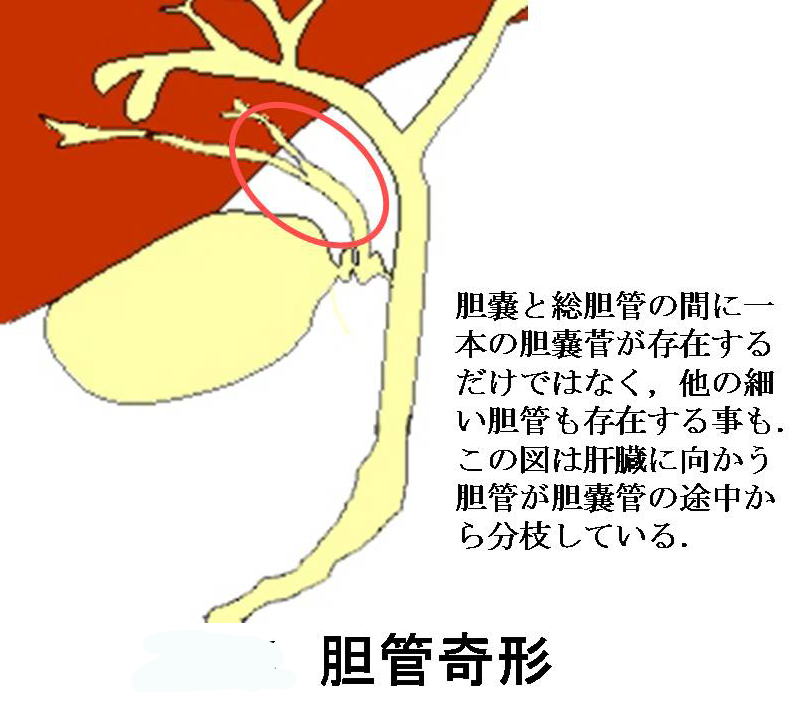

疾患での役割 [ ] 胆石症 [ ] 最大25%の人間が、、、およびで構成されたを持つ。 急性胆のう炎では、胆のうが浮腫などにより肥大しますが、慢性胆のう炎では胆のう壁が分厚くなり、胆のう自体のサイズは萎縮していきます。 写らない場合でも、胆嚢を映し出す造影剤があって、それを経口的、あるいは経静脈的に与えることにより胆嚢を映したり、内視鏡的逆行性胆管造影法によって、中にある石をみつけます。